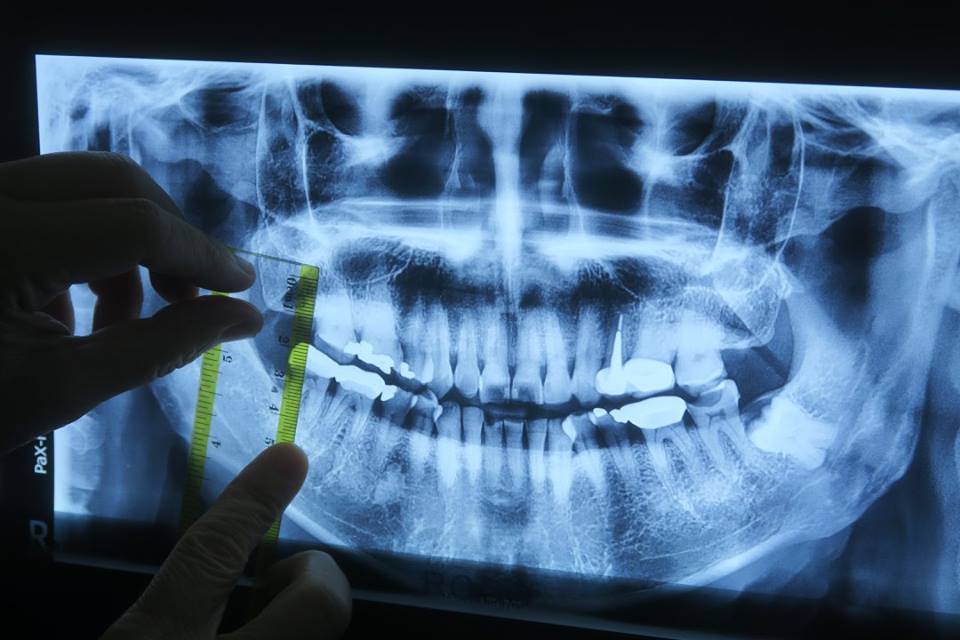

วานนี้แวะไปเอ็กซเรย์ที่ร้านหมอตี้ ได้ภาพนี้มา หมอบอกว่ากระดูกยังดีมาก ฟันที่ครอบไว้ก็ดูว่าดี แต่มี่ที่ต้องซ่อมหลายที่ ขออุดซึ่ล่างซ้ายซะก่อน ส่วนซี่ขวาบนที่ให้ยาบรรเทาปวดไปแล้วผมก็ไม่ได้กินนั้น ดันหายปวด แต่เกิดปวดมากที่ซี่ล่างขวาแบบแตะไม่ได้เลย ผมกินได้แต่ข้ามต้ม ไข่ตุ๋น และ ขนมจีนน้ำยา แบบ "ดูด ๆ" เอาเท่านั้น